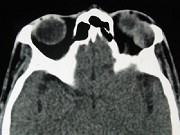

问题 女,36岁,左眼眶外上部可触及一无痛性包块有2年,眼球向内下方突出,CT检查如图,最可能诊断为()

选项 A.泪腺良性混合瘤 B.泪腺恶性上皮性肿瘤 C.炎性假瘤 D.淋巴瘤 E.淋巴瘤样增生

答案 A